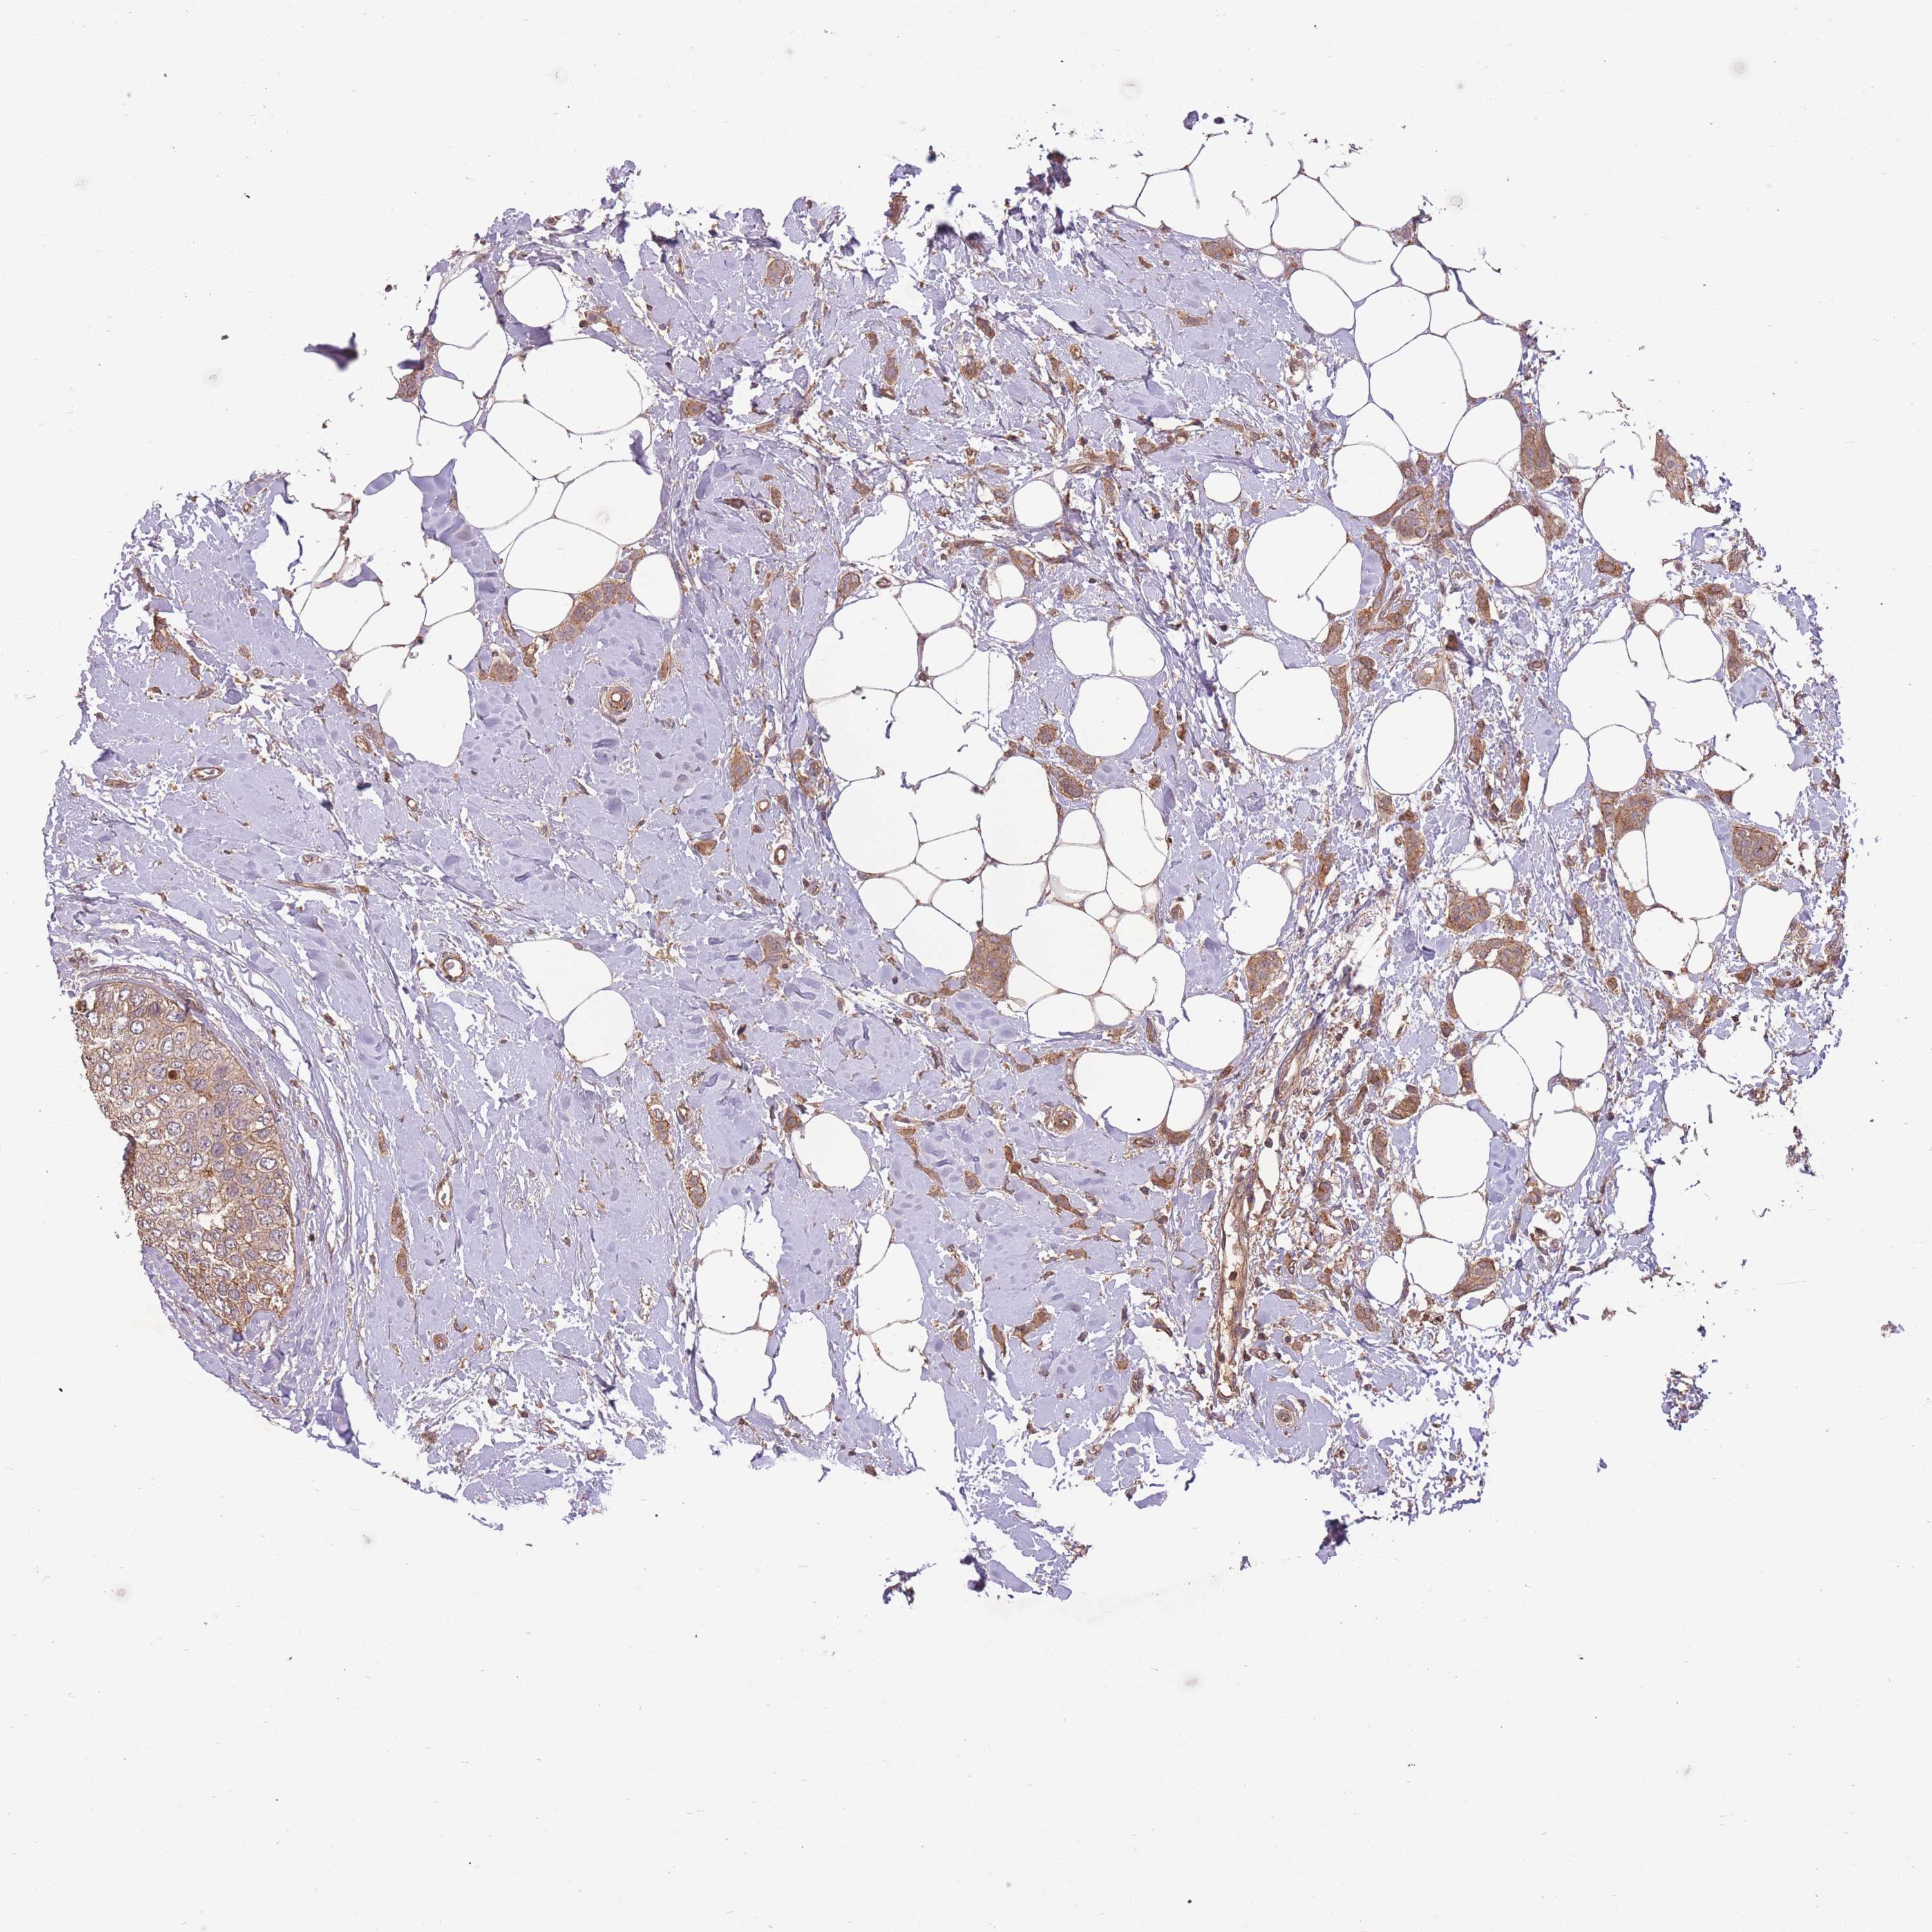

CANCER BREAST CANCER Show tissue menu

BRCA TCGA BRCA VALIDATION PROTEIN EXPRESSION

Breast cancer

Human cancer